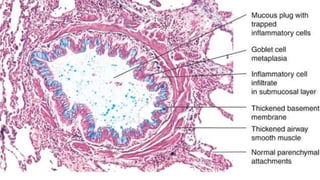

Pathology

•Airways

•parenchyma

•vasculature.

Chronic

inflammation